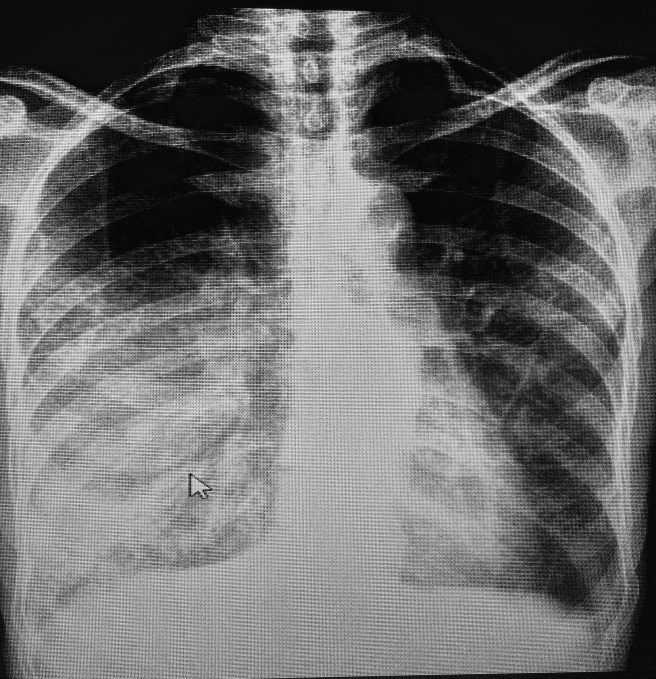

Imagem: broncograma aéreo

Faz tempo que não vejo um broncograma tão evidente. Paciente PVHA e tabagista, em abandono terapêutico.